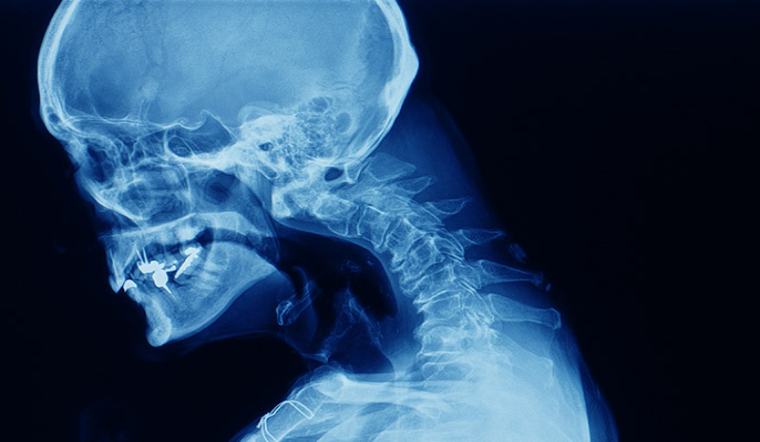

Gù lưng là gì?Gù lưng (Kyphosis) là tình trạng cột sống bị cong dần về phía trước, làm biến dạng phần lưng phía trên của bạn, khiến cơ thể bạn trở nên khòm đi. Nguyên nhân của hiện tượng này rất đa dạng, cũng có thể do chất lượng xương giảm ở người già và dị tật hoặc khớp xương cột sống bị chèn ép ở trẻ em.

Trong trường hợp nhẹ, tình trạng này không cần điều trị, chỉ cần đeo nẹp hoặc tập luyện để cải thiện tư thế và tăng cường sức bền của xương cột sống. Tuy nhiên, nếu tiếp tục để nó nghiêm trọng hơn thì cột sống có thể đau đớn, biến dạng cấu trúc và ảnh hưởng đến hô hấp. Trong trường hợp này, nên tham khảo ý kiến bác sĩ để được chỉ định mổ chỉnh hình kịp thời.